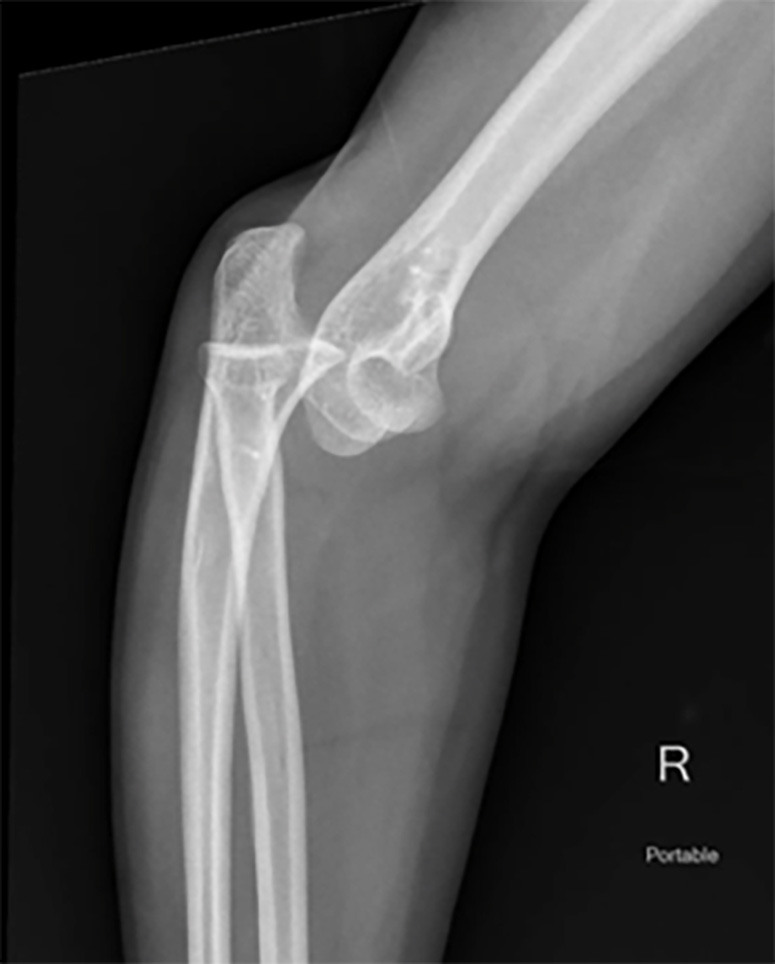

Elbow Dislocation

Elbow dislocations are the most common pediatric major joint dislocations and the second most common dislocations in adults. The mechanism typically involves a FOOSH resulting in a posterior dislocation.27 A thorough neurovascular examination is warranted given the proximity of the brachial artery, ulnar nerve, and median nerve; these injuries less commonly involve the radial nerve.27 X-ray is the preferred imaging modality (see Figures 3 and 4), with CT imaging considered for complex injuries involving surgical planning.28 After neurovascular assessment and imaging confirms the diagnosis, expedited reduction is indicated. Various reduction techniques are summarized in Table 2 and include:

Figure 3. Posterior Elbow Dislocation on Lateral View |

![]() |

Image courtesy of Hunter Roberts, MD. |